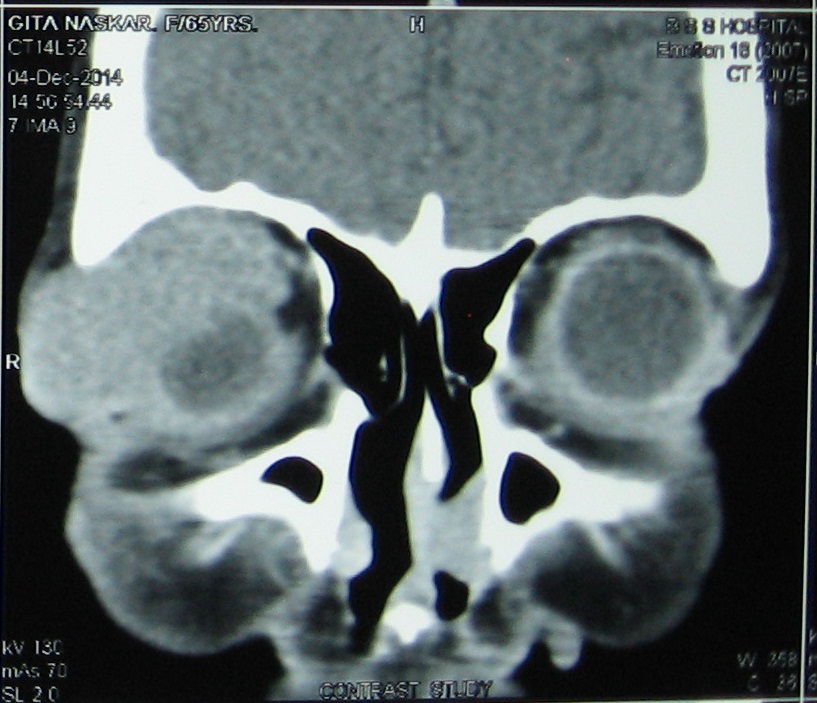

Primary Non-Hodgkins lymphoma of the orbit is a rare presentation and the diffuse large B-cell lymphoma (DLCL) type of histology is much less commoner than the mucosa associated lymphoid tissue (MALT) and follicular lymphoma. A 70 years female patient presented with palpable mass arising from right orbit and proptosis of the right eye. CT scan suggested homogenous enhancing soft tissue mass affecting right lacrimal region without any bony destruction. Biopsy confirmed it to be a case of Primary non-Hodgkins lymphoma of diffuse large B-cell type with strongly positive CD 20. She was given 6 cycles of chemotherapy with R-CHOP after surgery. The patient is now asymptomatic one year after the last cycle of the chemotherapy.